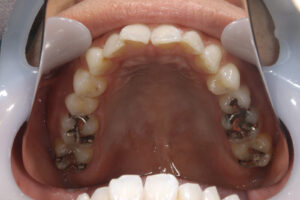

Ceramic inlay

ceramic onlay

Ceramic inlay, ceramic onlay, ceramic

Ceramic inlay, ceramic onlay,

- セラミックインレー・アンレー

内: セラミックインレー1本/80,000円、 セラミックアンレー80,000円 - 治療期間

- 他の歯科医院にて部分的な治療を受けたが、転居をきっかけに、見た目が良くない・噛めないとのことで再治療を希望された。他の医院に行こうとしたところ知り合いに当医院を勧められ来院した。アングルクラスⅠであった。

- 全顎的に着色が見られ、天然歯の変色が見られた。アングルクラスⅠで上下顎前歯部に叢生が見られ、クリーニングの後、上下顎臼歯部にセラミックインレー・アンレーを装着した。

- 審美的な仕上がりで、患者自身も満足した。半年経過し良好である。

現在は2〜3ヶ月おきのメインテナンス中である。

セラミックインレー・アンレーには欠け易いといったリスクがあるためナイトガードは必須である。

特に清掃が重要である。